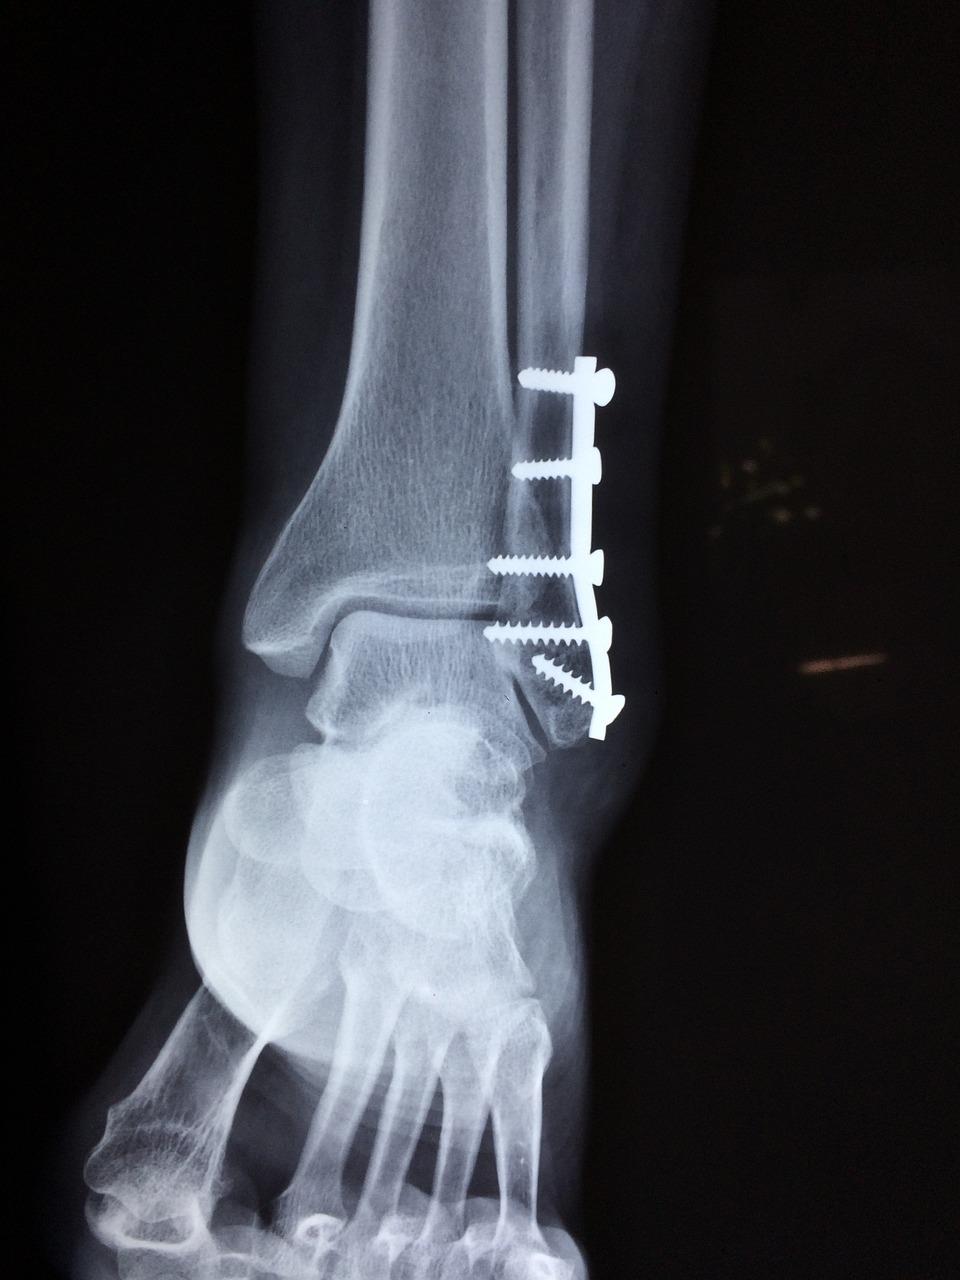

Wat is Orthopedie? Orthopedie is het medische specialisme dat zich bezighoudt met de behandeling van aandoeningen en letsels aan het bewegingsapparaat, waaronder botten, gewrichten, spieren, pezen en ligamenten. In Emmen